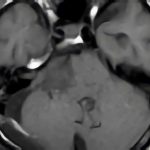

症例 '17年2月

No.

20

※ 画像をクリックすると拡大表示します。症例No.は平成29年から起算しています。

年_番号

手術年月

患者年齢

’17_20

'17年2月

50代

病名

術式

備考

嗅溝部髄膜腫

経鼻的腫瘍摘出術

断層撮影

手術前

1

手術前2

手術後